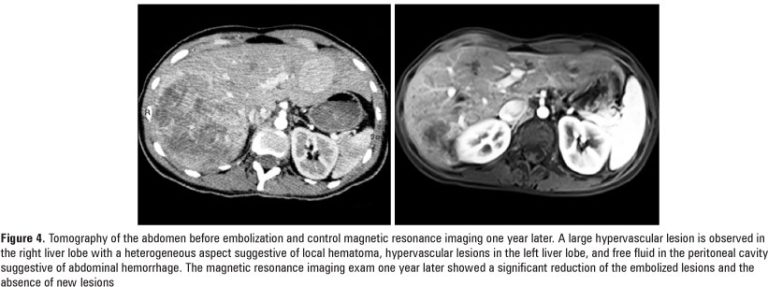

Hepatocellular adenoma is a rare benign tumor that was increasingly diagnosed in the 1980s and 1990s. This increase has been attributed to the widespread use of oral hormonal contraceptives and the broader availability and advances of radiological tests. We report two cases of patients with large hepatic adenomas who were subjected to minimally invasive treatment using arterial embolization. One case underwent elective embolization due to the presence of multiple adenomas and recent bleeding in one of the nodules. The second […]

Keywords: Adenoma, liver cells; Case reports; Embolization, therapeutic; Liver